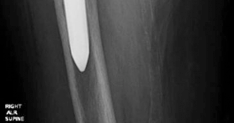

- Standard Radiographs: Anteroposterior (AP) pelvis, frog-leg lateral, and a true lateral of the affected hip are essential. These provide initial assessment of component position, subsidence, osteolysis, and general bone architecture. Stress views may be helpful for suspected pelvic discontinuity.

- This image could be a post-operative radiograph showcasing the completed reconstruction with an augment and revision cup. -

- Another post-operative X-ray providing a different view or illustrating a similar case. -

- A close-up radiographic view highlighting the augment and its screw fixation, along with the acetabular cup. -